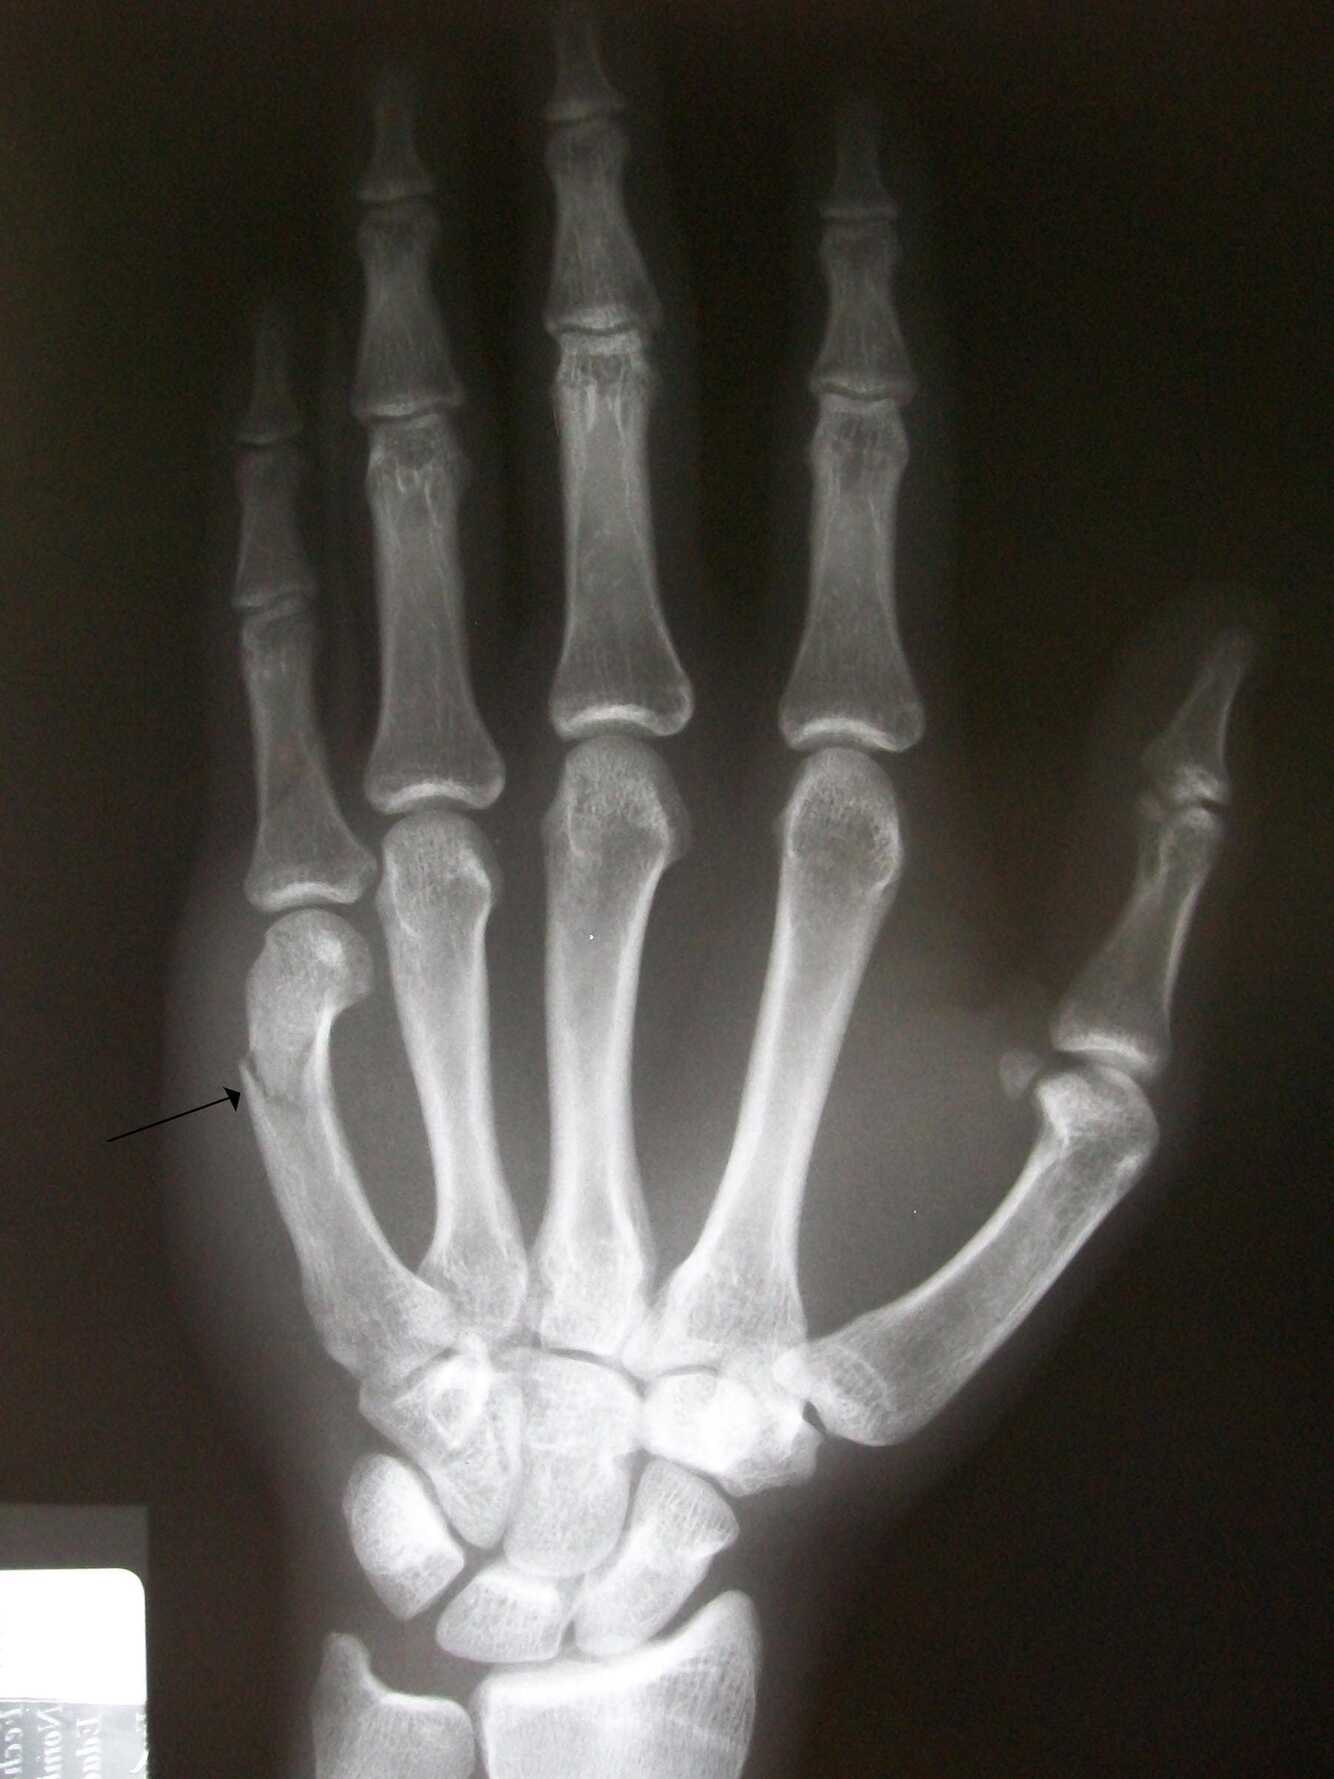

vad är en bennettsfraktur?

vilken del? etiologi? symtom? handläggning?

A

• En Bennettfraktur innebär en fraktur i tummens innersta led CMC1, där ena metacarpalbensfragmentet (huvudfragmentet) disloceras på grund av drag från abductor pollicis longus-senan.

• Tillståndet orsakas ofta av fallskada eller av våld mot en knuten hand och tumme.

• typiska symptom är svullnad och ömhet över det frakturerade området.

• Diagnosen ställs med hjälp av röntgen i två plan.

• Tillståndet behandlas med operation och därefter gips i 4-6 veckor.

• Kan ge komplikationer i form av artrosutveckling.